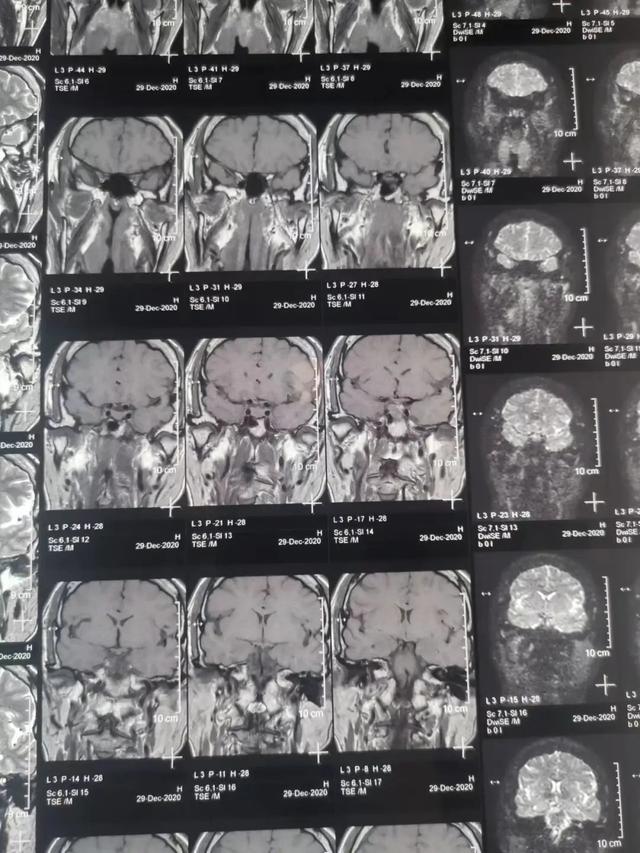

看不清东西未必是眼的错,可能是垂体瘤在作祟!今天就来跟大家介绍这种隐蔽性较强的垂体瘤到底还有什么症状,对身体的影响及其治疗手段。 垂体瘤是一种良性腺瘤 垂体瘤是一种良性腺瘤... 垂体瘤多发生于垂体前叶,也就是我们的腺垂体。 垂体瘤可见于任何年龄段的人群,男性相对多于女性。无症状的垂体瘤或垂体微腺瘤占多数。...

看不清东西,未必是眼睛的错!可能是垂体瘤!今天就来跟大家介绍这种隐蔽性较强的垂体瘤到底还有什么症状,对身体的影响及其治疗手段。 01 垂体瘤是一种良性腺瘤 垂体瘤是一种良性腺... 垂体瘤多发生于垂体前叶,也就是我们的腺垂体。 垂体瘤可见于任何年龄段的人群,男性相对多于女性。无症状的垂体瘤或垂体微腺瘤占多数。...